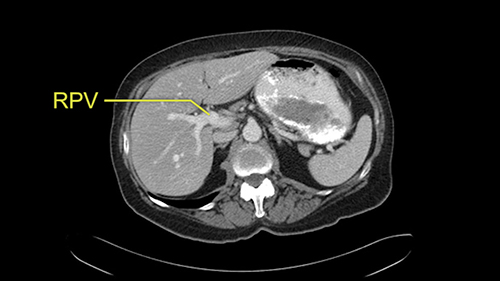

![[RHA]](jpg/preop_sg_moment3.jpg)

The only other most important feature that I usually consider is the portal vein split or the bifurcation, especially if doing a major liver resection like a right lobe. I like to look at the length of the common right portal vein trunk which looks like its probably long enough to put a stapler on. Final decision would be in the OR. If it wasn’t long enough and I was concerned about injuring the bifurcation or the left portal vein, then I would divide the Segment 5-8 and 6-7 portal tracks individually.

![[LPV]](jpg/preop_sg_moment4b.jpg)

This patient has an interesting minor anomaly with what looks like a Segment 7 portal vein coming off close to the bifurcation of the right portal vein but again if I was doing a right lobe which is my plan, this wouldn’t be an issue.